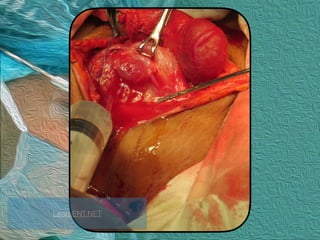

Central Compartment Neck

Dissection